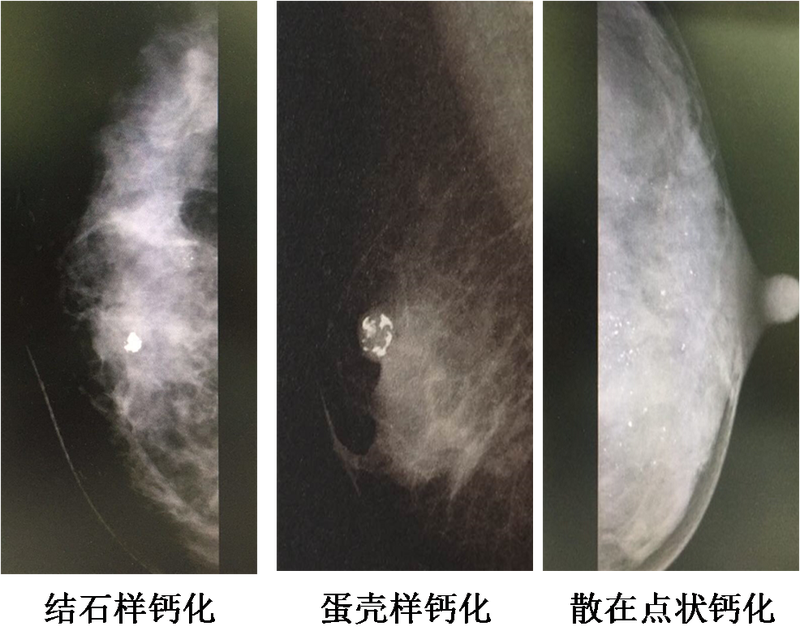

乳腺鈣化灶是何方神圣?長啥樣?通俗地說,就是乳腺鉬靶黑膠片上的白色“亮點點”。針對乳腺的三個檢查:B超、鉬靶、磁共振,乳腺鉬靶對鈣化灶最敏感。在鉬靶的黑膠片上,不僅可以看到鈣化灶的分布走向圖,還可以根據(jù)鈣化灶的長相來判斷病灶的性質(zhì)。那么,乳腺鈣化灶如何形成的?有乳腺鈣化灶,就有癌變傾向嗎? 乳腺鈣化灶到底離乳腺癌有多遠呢? 乳腺鈣化灶是如何形成的? 其實,乳腺鈣化灶就是一些鈣鹽沉積于乳腺中??梢允侨橹俜e殘留的沉積物,也可以是乳腺炎癥的滲出物;可以是纖維腺瘤中堅硬如石的粗大鈣化灶,也可以是乳腺癌中惡性腫瘤細胞的壞死殘骸。 人體內(nèi)許多器官都有可能形成鈣化灶。例如:肝臟鈣化灶與肝內(nèi)膽管結(jié)石有關(guān);肺內(nèi)鈣化灶,基本以良性病變?yōu)橹?;甲狀腺鈣化灶,有三分之一是惡性病變;乳房鈣化灶,就要具體情況具體分析了: 乳腺良性鈣化灶長啥樣? 乳腺良性鈣化灶通常表現(xiàn)為散發(fā)的、粗大的鈣化灶,有時為雙側(cè)的,或伴有其他良性病變。也就是說,乳腺病、乳腺小葉增生、哺乳后奶水未完全吸收、乳腺炎滲出壞死等,都有可能存在乳腺鈣化灶。 乳腺惡性鈣化灶長啥樣? 乳腺惡性鈣化灶主要表現(xiàn)為聚集的、細小的鈣化灶,有時沿乳腺導管分布,如同樹枝狀;有時新出現(xiàn)的或新增加的鈣化灶,惡性的可能也較大。乳腺癌或?qū)Ч軆?nèi)癌有時會伴有惡性鈣化灶。 乳腺可疑鈣化灶長啥樣? 乳腺可疑鈣化灶是指鉬靶報告上顯示BI-RADS 4a的鈣化灶,分布較聚集,顆粒小,無法準確評估,常常需要磁共振來協(xié)助判斷病變性質(zhì),或者手術(shù)活檢明確良惡性??梢赦}化灶中僅20%病變?yōu)閻盒?,并且絕大多數(shù)是導管內(nèi)癌。 因此,乳腺鈣化灶形形色色,大部分還是以BI-RADS 3的良性病灶為主。BI-RADS 4a的鈣化灶也僅有5%的病變?yōu)槿橄俳櫺园?。只要穩(wěn)定的、沒有新發(fā)現(xiàn)的鈣化灶,它離乳腺癌的距離還有十萬八千里。